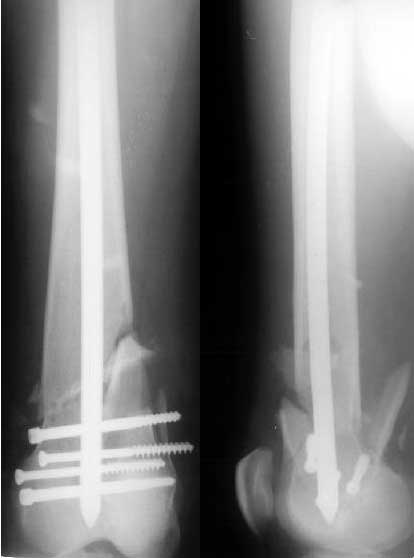

Такой вариант мы не рассматривали как чрезмерно травматичный. Как и предполагали, удалось сопоставить отломки стержня и после удаления

винтов вытолкнуть нижний кусок дистально. И через это же отверстие, используя стандартный доступ с расщеплением сухожилия 4-главой мышцы,

ретроградно забили другой стержень диаметром опять 11 мм - толще у нас пока таких нет. Обнадеживает то, что диаметр утолщенной части стержня 12 мм, а отверстие - 5 мм.

Некоторые зарубежные коллеги все-таки склонялись бы к пластине, но нового поколения, типа LISS, с резьбовой фиксацией винтов, вводимой через небольшой разрез. И удаляли бы отломки стержня через верх - им легко говорить, имея специальный инструментарий для этого...

You said: " but inserted from below. I locked it statically at the moment."

I have a query. From the picture it looks as if you used the usual proximal end as the distal end of nail.

This means that you would have got the help of the zig to lock the distal end(near the knee). If this is correct how did you lock the holes near the trochanter?

I didn't use the jig in the case. All screws were inserted using a self-made "radiolucent drill bit". I mentioned this before - tip of 2 mm wire is flattened to 3,5 mm and sharpened. It can be positioned over the hole using a plastic handle. The one is made from a toy of my son :-) The technique works fine for me.